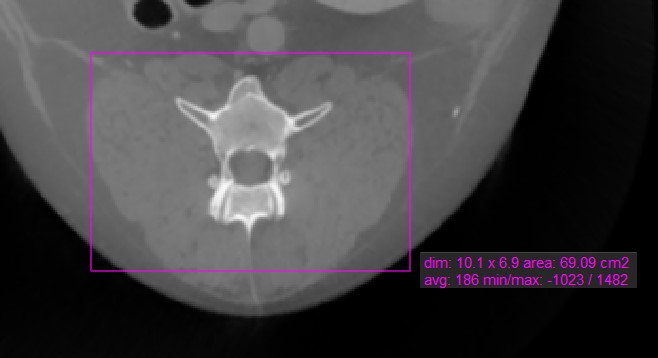

Rechteck¶

Das Werkzeug Rechteck ermöglicht es dem Benutzer, einen rechteckigen Bereich auf der aktiven Bildschicht zu markieren.

Wählen Sie das Werkzeug Rechteck aus und weisen Sie es einer der verfügbaren Maustasten zu. Starten Sie die Messung, indem Sie auf die aktive Bildschicht klicken und die Maus ziehen, um eine rechteckige Form zu erstellen. Lassen Sie die Maus los, wenn die Größe des markierten Bereichs zufriedenstellend ist.

Alle verfügbaren Messwerte werden zusammen mit der Messung angezeigt.

Ändern Sie den markierten Bereich, indem Sie einen der vier Punkte der rechteckigen Form mit dem Werkzeug Standard verschieben.